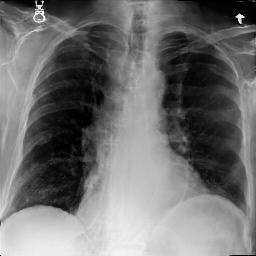

Fig. 3: Anonymization results. Real images XRX_{R} randomly selected from the training, validation, and test sets are displayed in the first column. The corresponding reconstructed images X^R\hat{X}_{R} are displayed in the second column. The anonymized images XAX_{A} are displayed in the last three columns.

Qualitative Results The visualization results are shown in Fig. 3. In this figure, the anonymized images optimized using only the utility loss ut\mathcal{L}_{ut} (column 3) exhibit greater visual similarity to their real counterparts (column 1), while those optimized using only the identity loss id\mathcal{L}_{id} (column 4) appear more distinct from their originals. Additionally, the anonymized images optimized with both the ut\mathcal{L}_{ut} and the id\mathcal{L}_{id} (column 5) strike a balance, appearing more realistic by simultaneously considering both identity removal and utility preservation.